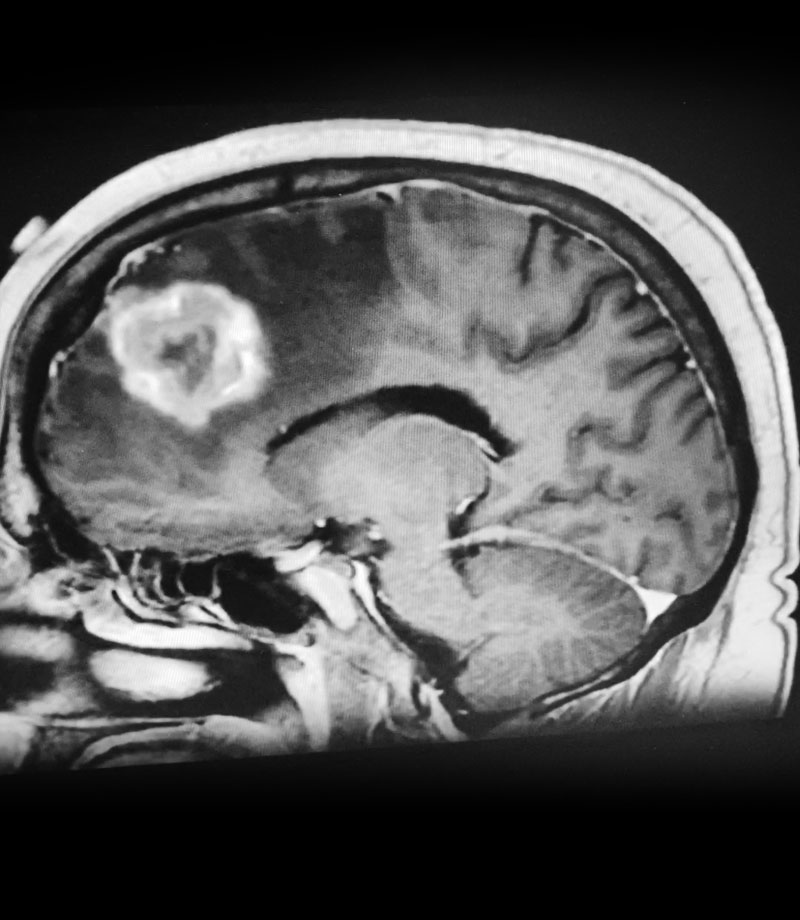

Postoperative images looked good (Figure 3). The patient felt better after surgery. His headaches were much better and he started to feel stronger. He was discharged after a brief hospital stay. He tapered his steroids to off. He will get follow up MRI images every few months. If tumor does recur, repeat radiosurgery would be performed.

Figure 3: Post operative CT scan.